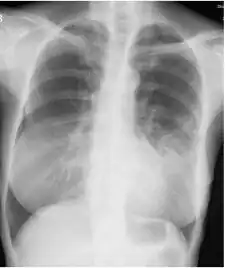

Image indicate bronchodilation, centrilobular granular shadow, and consolidation

Chest radiograph